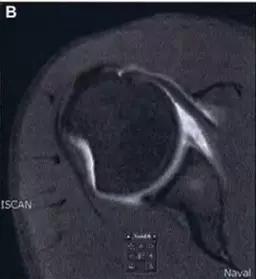

Hill-Sachs 损伤的 MR 片(来源:Hill-Sachs Injuries of the Shoulder)

- 肩关节前脱位时发生的肱骨头后外侧凹陷性骨折,是经典的 Hill-Sachs 损伤(Hill-Sachs lesion);

- 而肩关节后脱位时发生的肱骨头前内侧凹陷性骨折,是反 Hill-Sachs 损伤(Reverse Hill-Sachs lesion/ McLaughlin lesion)。